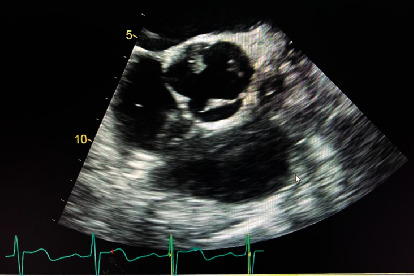

Abstract Image